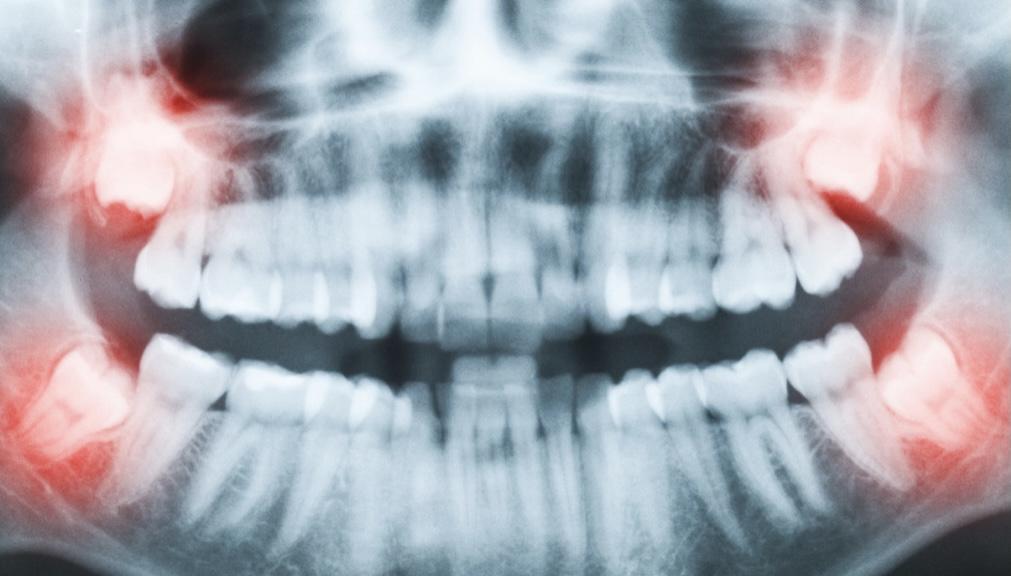

假如吃了止痛藥還是果不,甚至出現(xiàn)了拔牙一側(cè)頭疼,那么有可能出現(xiàn)了干槽癥,應該及時找醫(yī)生進行復診。

(面部腫脹、疼痛嚴重者隨時復診)